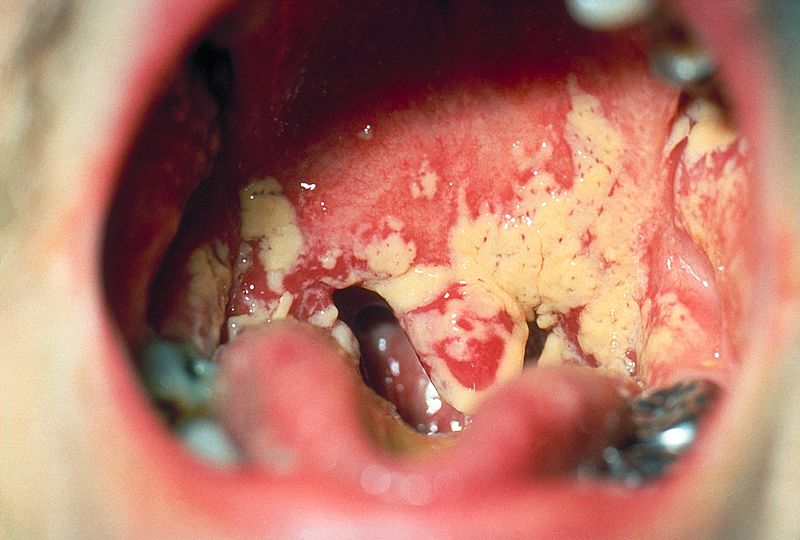

Oral Candidiasis

Candida is a yeast organism that is often present in minute amounts in regular saliva, is a frequent cause of oral thrush infection.

Candida is harmless to healthy individuals.

Candida overgrowth can happen in people whose immune systems have been compromised by disease or drugs.

As a result, the tissues in the mouth become inflamed, and “thrush” (a whitish crust or coating on the tongue’s surface) develops.

Risk factors for oral candidiasis (“thrush”) include:

Thrush can occasionally progress into the potentially dangerous disorder oropharyngeal candidiasis (OPC).